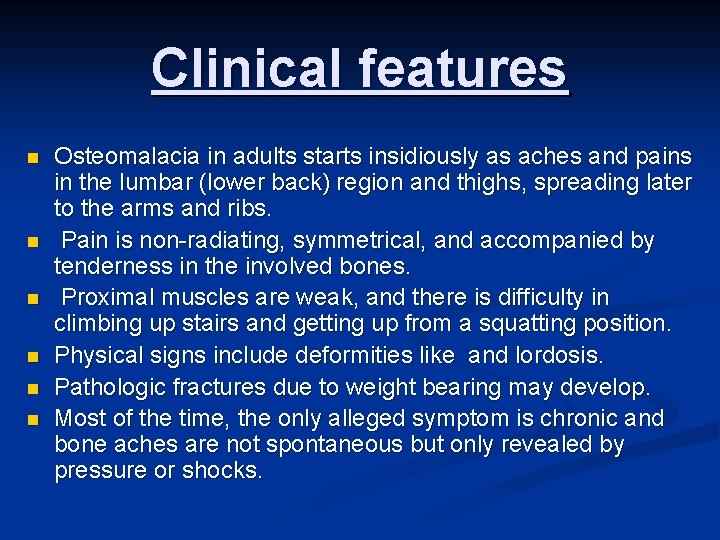

Clinical features n n n Osteomalacia in adults starts insidiously as aches and pains in the lumbar (lower back) region and thighs, spreading later to the arms and ribs. Pain is non-radiating, symmetrical, and accompanied by tenderness in the involved bones. Proximal muscles are weak, and there is difficulty in climbing up stairs and getting up from a squatting position. Physical signs include deformities like and lordosis. Pathologic fractures due to weight bearing may develop. Most of the time, the only alleged symptom is chronic and bone aches are not spontaneous but only revealed by pressure or shocks.

RICKETS, OSTEOMALACIA CLINICAL FEATURES: n Rickets - Tetany , convulsions, failure to thrive, restlessness, muscular flaccidity. Flattening of skull (craniotabes), Thickening of wrists from epiphyseal overgrowth, Stunted growth, Rickety rosary, spinal curvature, Coxa vara, bowing, # of long bones n Osteomalacia, - Aches and pains, muscle weakness loss of height, stress #s.

Manifestations of Osteomalacia Localized bone pain Difficulty walking Low back pain Fractures are common, and delayed healing occurs Muscular weakness Weight loss Progressive deformities of the spine (kyphosis)